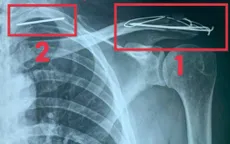

Ca bệnh hy hữu: Đinh Kirschner gãy, di trú vào phổi sau phẫu thuật vai

VTV.vn - Nam bệnh nhân 60 tuổi ở Quảng Trị bị gãy đinh Kirschner, di trú vào phổi trái sau phẫu thuật vai 3 năm trước, suýt nguy hiểm tính mạng.